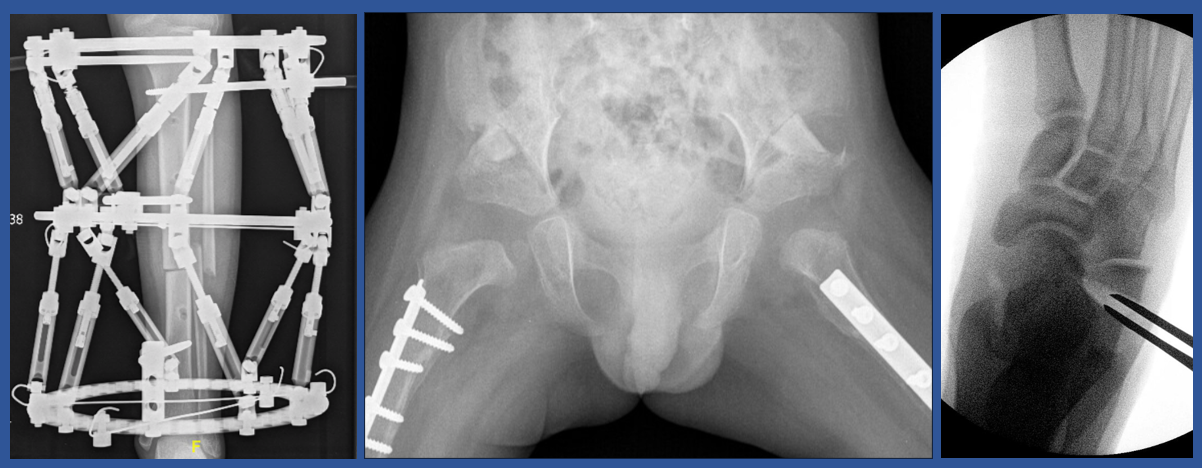

This website is borne out of my passion for the depth and complexity of Pediatric Orthopaedics. I am very fortunate that I really enjoy my job and I hope this enthusiasm is carried over into the content on this website. I initially started out posting cases on LinkedIn to help patients and parents understand Pediatric Orthopedic Treatments with visual guides but also to generate scope for ongoing discourse with colleagues across the globe. By sharing cases I hoped that patients and their families would benefit by understanding what treatment for common Pediatric Orthopedic conditions entails using case examples that I had treated. I also hoped it would pique my colleagues curiosity sufficiently that they would contribute insights, technical tips and much valued critique of my surgical endeavours. Over time I felt that it would be better to compile these cases into a personal website which could be readily accessible and where interesed readers could subscribe to be notified of new case additions.